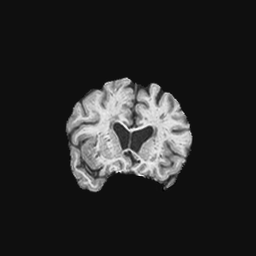

Exp. 2: Fetal brain data is used to test the robustness of our approach under real conditions. Fetuses younger than 30 weeks very often move a lot during examination. Fast MRI sequences allow artifact free acquisition of individual slices but motion between slices corrupts consistent 3D information. Fig. 3 shows that our method is able to accurately predict also under these conditions. For this experiment we use from three orthogonally overlapping stacks of ssFSE slices covering the fetal brain with approximately 20-30 slices each. We are ignoring the stack transformations relative to the scanner and treat each individually. For , 28 clinically approved motion compensated brain reconstructions are resampled into a volume with spacing. A density of 500 unique sampling normals has been chosen via the Fibonacci sphere sampling method with 25 sampling planes evenly spaced between -25 to +25 on the Z-axis. This gives a plane spacing of 2mm, sampling only the middle portion of the fetal brain. Training took approximately 10hrs for 30 epochs. Prediction, i.e., the forward pass through the network, takes approx. 12 ms/slice.

0..5.2 Exp. 2:

Slices, from a motion corrupted MRI stack, are segmented and cropped. Since there is no ground truth for the queried images, an arbitrary fetal atlas is used for visualization in Fig. 11 and 12.